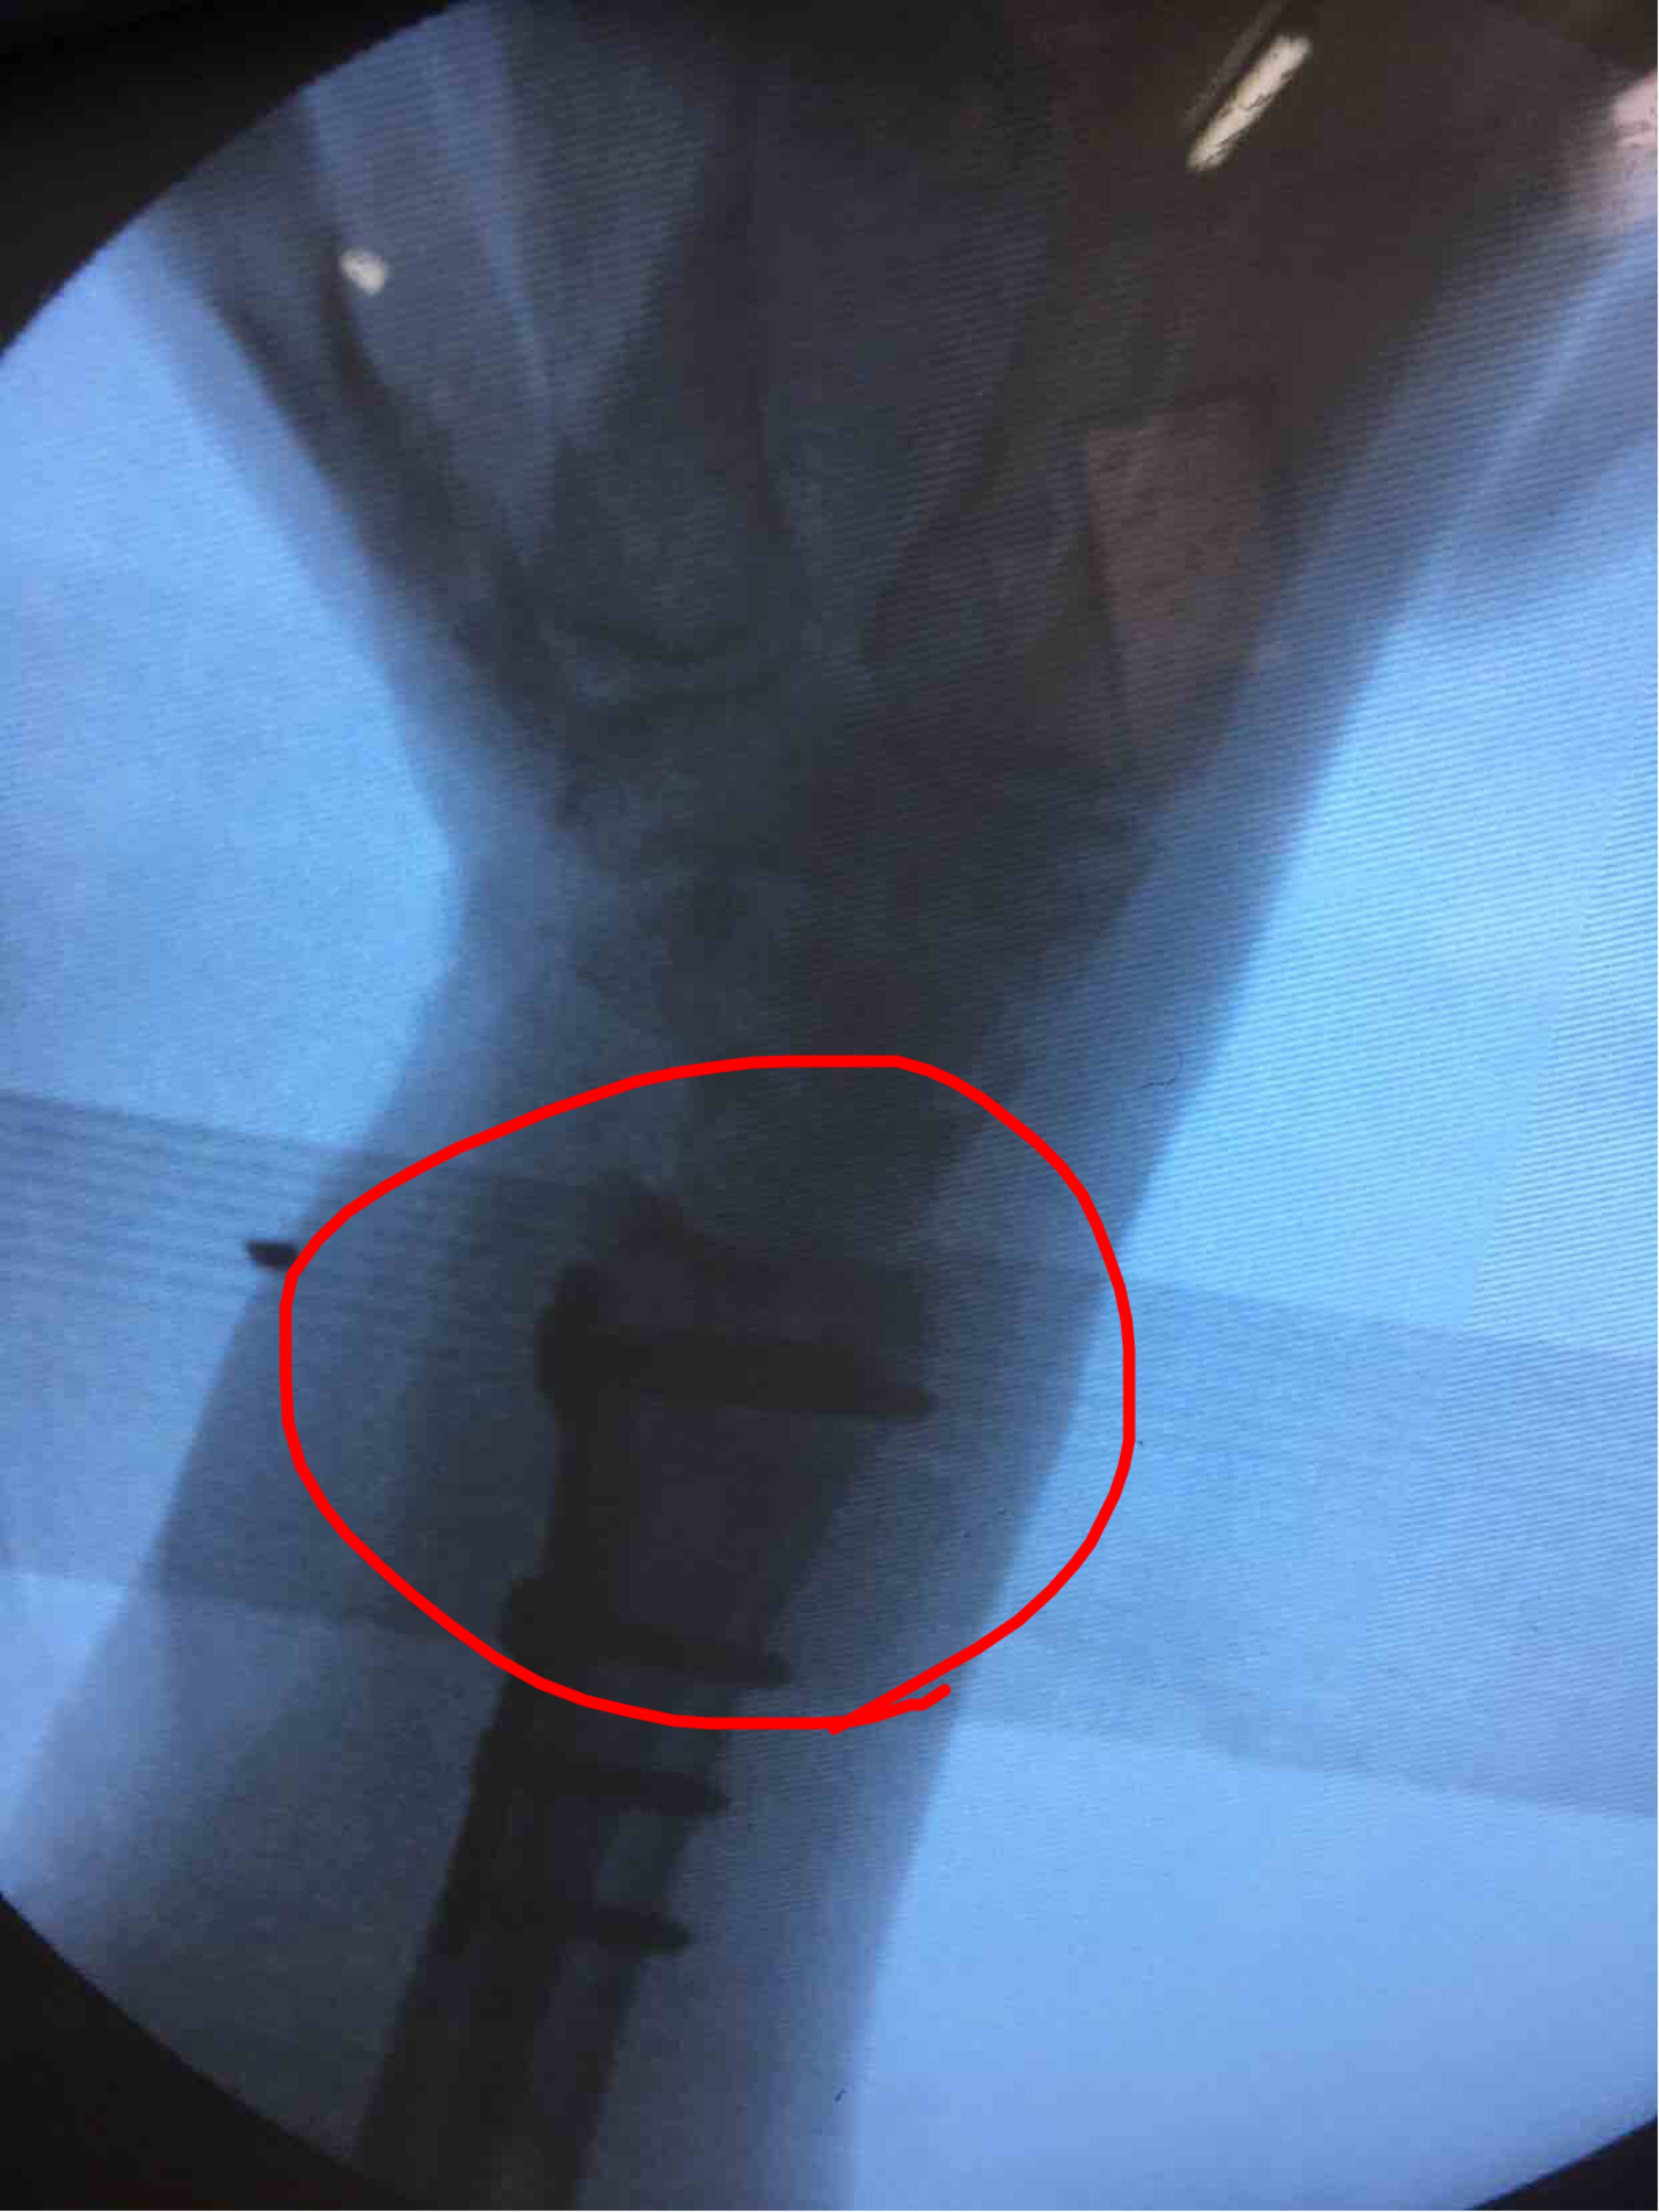

摔伤后腕部肿痛,活动受限4天入院。4天前在外院行手法整复,复查关节面塌陷,尺偏角掌倾角变小,后来我院就诊。

诊断:右侧克雷氏粉碎性骨折完善术前准备,在臂丛麻醉下行切复内固定术,术后抗炎,消肿等对症处理。